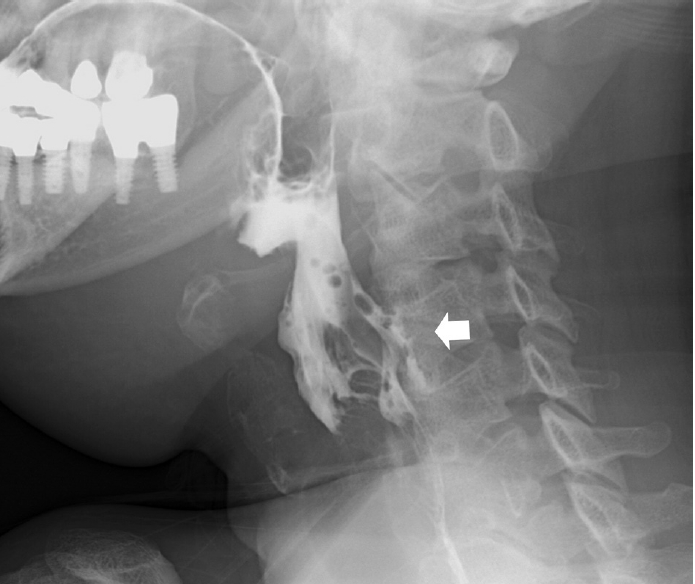

47세 남자 환자가 3일 전부터 발생한 좌측 턱 부위의 부종이 있어 본원 이비인후과 외래로 내원하였다. 과거력상 30갑년의 흡연력, 당뇨 과거력이 있었고, 최근 6개월간 10% 체중감소를 호소하였다. 신체검진상 좌측 경부 level II, III에 걸쳐서 단단하고 고정성의 종물이 다발성으로 촉진되었고, 좌측 편도와에 ulcerofungating 양상의 종물을 포함한 편도 비대가 관찰되어 외래에서 국소마취하에 조직검사를 시행한 결과, p16 양성 편평세포암종이 보고되었다. 이후 시행한 영상검사상, 경부 전산화단층촬영 및 자기공명영상에서 좌측 편도와에 국한된 장경 3.6 cm 크기의 종물 및 좌측 경부 level II, III에 장경 6 cm 이하의 다발성의 림프절 비대 및 응집 소견이 확인되었으나 전신 양전자단층촬영 검사상 원격 전이 소견은 보이지 않았다(Fig. 1). The American Joint Committee on Cancer 8판에 따라 cT2N1M0 병기의 편도암 의심하에 환자의 젊은 나이와 치료 후 사회적 활동을 고려하여 경구강 로봇 수술과 근치적 경부절제술을 계획하였다.

환자는 술후 동시항암방사선 치료 종료 6주 후부터 호흡곤란 증상을 호소하여 방사선으로 인한 후두염 진단하에 3차례 입원 후 보존적인 치료를 하고 퇴원하였다. 이후 정기적 외래 추적 관찰 중 술후 동시항암방사선 치료 종료 후 21주째, 좌측 경부 level II에 작은 피부 결손 부위와 함께 혼탁성삼출물이 흘러나오는 것을 발견하였고, 당시 시행한 경부 전산화단층촬영 검사에서, 이전에는 보이지 않던 좌측 편도와에서 좌측 부인두공간으로 연결된 누공이 새로 형성된 것을 확인하였다(Fig. 3). 이에 따라 국소마취하 절개 배농술을 시행한 뒤, 피부 결손 부위에서 구인두 공간까지 이어지는 누공길(fistulous tract)을 확인한 이후, 배액관의 도관을 재단하고 경부에서 구인두 방향으로 이를 거치하여 지속적 음압 드레싱을 시행하였고, 이와 함께 비영양관 튜브를 통한 식사 및 정맥 내 항생제 치료를 시행하였다(Fig. 4). 치료를 유지하여 1달 뒤 시행한 경부 전산화단층촬영 검사에서 인두피부누공이 호전되지 않은 것을 확인하였고, 이에 따라 전신마취하 대흉근피판을 이용하여 결손 부위를 재건하였다(Fig. 5). 수술후 8일째 금식과 정맥 내 고영양 치료를 유지하던 중, 환자가 협조하지 않아 소량의 경구식이를 시작하였다. 수술 후 12일째 수술 부위 배액관을 통해 다시 타액이 유출되는 것을 확인하여 전신마취하에 경부 탐색술을 시행하였고, 피판 부위는 유지되고 있는 것을 확인하여 죽은조직제거술을 시행한 후 수술을 종료하였다. 환자는 금식을 다시 유지하였고 대흉근 피판재건술 이후 38일째 식도조영술을 시행하였으며, 좌측 이상와 부위에서 작은 누공이 추가로 확인되었으나(Fig. 6), 환자가 경구식이를 강하게 희망하여 2일 후 소량의 경구식이를 재개하였다. 이후 배액관의 배액량이 줄어드는 양상을 보이는데다 환자가 외래 통원치료를 희망하여 입원한 후 80일만에 배액관을 유지한 채로 퇴원하였다.